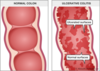

# UC Location & Pattern of Inflammation

Invariably **involves the rectum** and **may extend proximally** through the colon in a **continuous** fashion **Small intestine is unaffected** Skip lesions are **not** seen Inflammation is **limited to the mucosa**

# UC Colonoscopy

with biopsy Gold standard for diagnosis Helps to determine the extent of disease **Contraindicated during an acute exacerbation due to risk of intestinal perforation**- use steroids to calm before visualization Diffuse and continuous mucosal inflammation always involving the rectum **Friable mucosa** Pseudopolyps: raised areas caused by recurrent ulceration, healing, and scarring of the mucosa